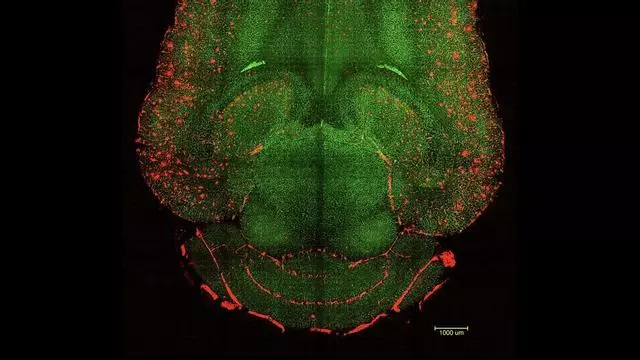

Imagen del cerebro de uno de los ratones tratados con estas inyecciones de nanopartículas. / IBEC

Un equipo internacional de científicos ha logrado un espectacular y prometedor avance en la lucha contra el alzhéimer. Un trabajo conjunto del Instituto de Bioingeniería de Catalunya (IBEC) y el Hospital West China de la Universidad de Sichuan (WCHSU) ha logrado revertir esta enfermedad neurodegenerativa en ratones mediante tres inyecciones de nanopartículas bioactivas.

Las primeras pruebas con estos compuestos reportan resultados que rozan lo extraordinario. Según explican los especialistas, esta terapia se aplicó en ratones de 12 meses, el equivalente a 60 años humanos, con síntomas de alzhéimer. En cuestión de horas se empezaron a ver cambios en su cerebro y días más tarde ya se vieron cambios positivos en su comportamiento y memoria.

También se observó que seis meses más tarde, cuando los animales tenían el cerebro de un nonagenario, los ratones ya no mostraban síntomas de la enfermedad sino que se comportaban como ejemplares completamente sanos. "El efecto a largo plazo se debe a la restauración del sistema vascular del cerebro. Una vez se reabre esta vía, el propio organismo empieza a eliminar las moléculas tóxicas y a recuperar su equilibrio", detalla Battaglia.